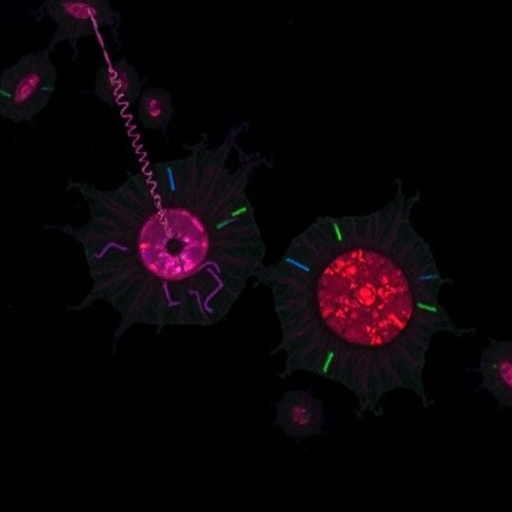

In a recent groundbreaking study published in Journal of Translational Medicine, researchers led by Zhu et al. have unveiled the intricate dynamics of extracellular vesicle DNA within recipient cells through a revolutionary imaging technique known as single-molecule localization microscopy (SMLM). This illuminating work delves deep into the role of extracellular vesicles (EVs) as mediators of cellular communication, unveiling the complexities of biological information transfer at the molecular level. By focusing on how these vesicles carry and deliver DNA, the study offers new pathways for understanding disease mechanisms and therapeutic interventions, particularly in cancer biology and regenerative medicine.

SMLM is a highly advanced imaging technique that surpasses the diffraction limit of conventional fluorescence microscopy. By precisely localizing individual fluorophores, researchers can achieve unprecedented spatial resolution that allows for the visualization of molecular interactions and dynamic cellular processes. In this study, the authors utilized SMLM to investigate the presence and localization of DNA within EVs and their subsequent delivery into recipient cells, leading to revelations about the pathways through which genetic information is transferred and utilized.

The findings from Zhu et al. underscore the remarkable ability of EVs to act as carriers for functional DNA, which can ultimately influence the behavior of recipient cells. This discovery sheds light on the biological significance of EVs in various contexts, ranging from physiological processes to pathological conditions such as cancer. By analyzing the spatial distribution of EV-associated DNA, the researchers highlighted crucial interactions between EVs and target cells, elucidating the molecular mechanisms underlying these interactions.